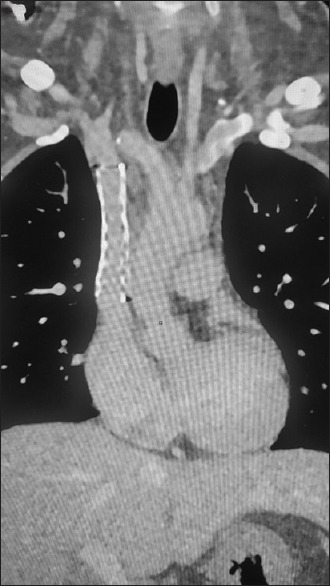

组织胞浆菌病表现为纤维化性纵隔炎和上腔静脉阻塞。

Histoplasmosis presenting as fibrosing mediastinitis and superior vena cava obstruction.